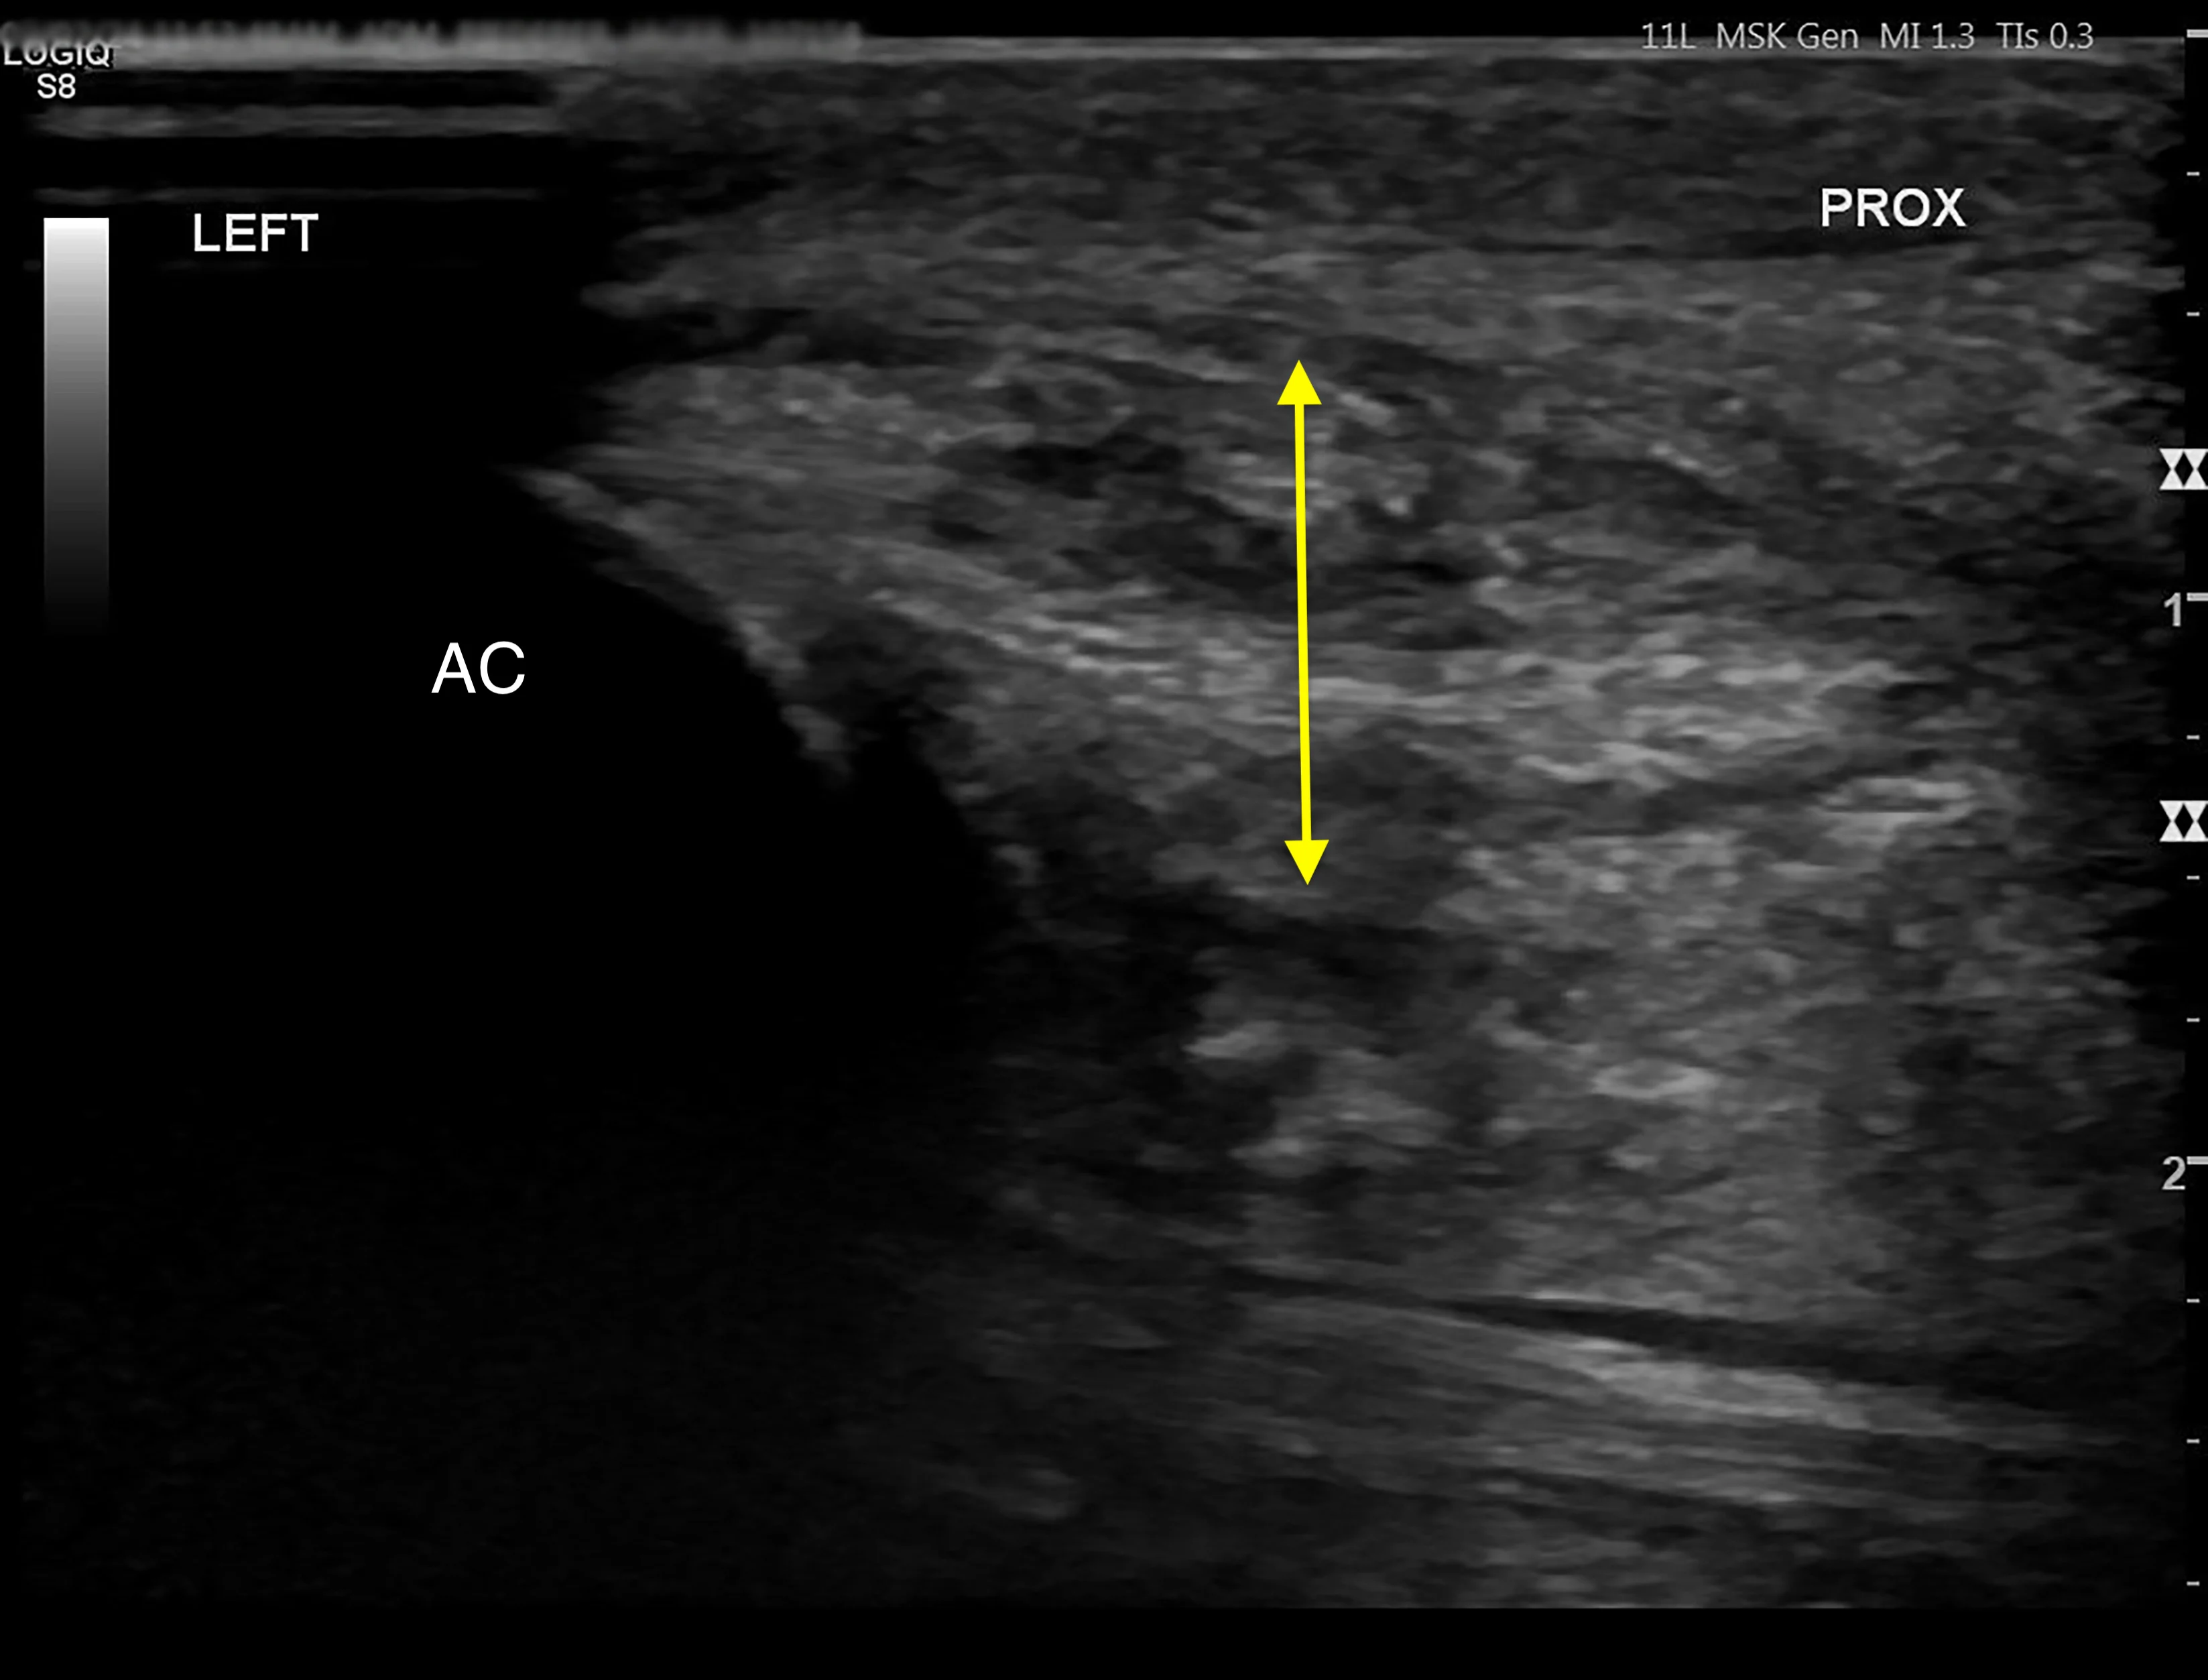

Based on the location of soft tissue swelling, a strain injury to the tendon of the flexor carpi ulnaris at the insertion on the accessory carpal bone was suspected. Musculoskeletal ultrasonography of the left and right antebrachium was performed for comparison and revealed significant tendon disruption of the insertions of the humeral and ulnar heads of the left flexor carpi ulnaris (Figure 3).8 Hyperechoic regions indicated fibrosis, which is typical of chronic injury.

Ultrasound images of the abnormal left flexor tendon (A) and contralateral normal right flexor tendon (B) at the insertion on the accessory carpal bone (arrows). The irregular fiber pattern and regions of hypoechoic and hyperechoic tendon in the left thoracic limb indicate tendon fiber disruption and fibrosis consistent with chronic injury. AC, accessory carpal bone